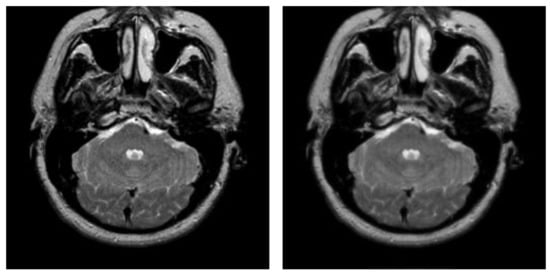

After hybrid L1 − L0 layer decomposition, the base layer of original image is used for segmentation in the framework of the proposed algorithm. Figure 7 displays an example of decomposition. In Figure 7, the first column contains two original images, and the second column contains two corresponding base layers. From Figure 7b, it can be seen that the base layers are visually smooth, and eliminate some weak edges.

Figure 7.

Original images and their corresponding base layers. (a) Original images, (b) base layers.